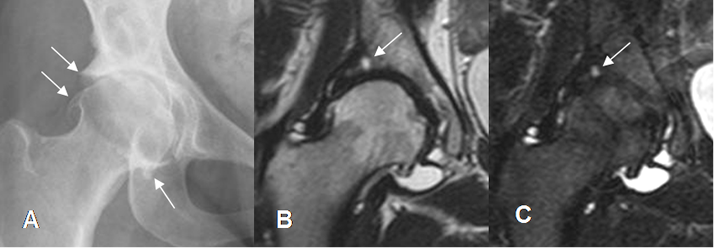

Fig 92. Artropatía degenerativa.

A: Rx AP. Disminución asimétrica del espacio articular y formación de osteofitos.

B: RM coronal en T2 y C: RM coronal en STIR. Además de los osteofitos, existe lesión osteocondral en el borde acetabular superior.